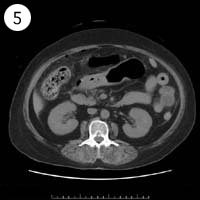

57歳 女性

単純CT

造影CT